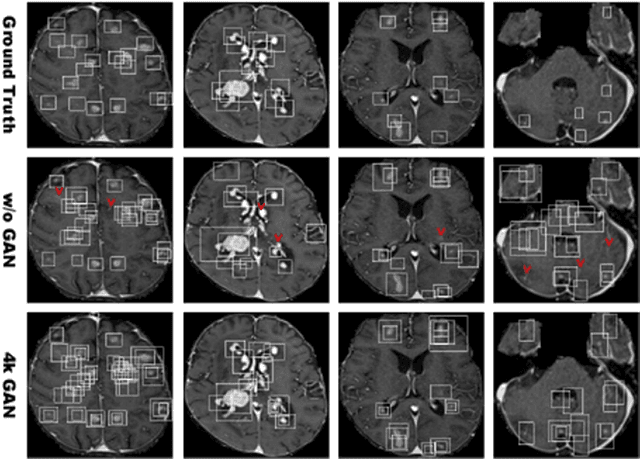

Abstract:Convolutional Neural Network (CNN)-based accurate prediction typically requires large-scale annotated training data. In Medical Imaging, however, both obtaining medical data and annotating them by expert physicians are challenging; to overcome this lack of data, Data Augmentation (DA) using Generative Adversarial Networks (GANs) is essential, since they can synthesize additional annotated training data to handle small and fragmented medical images from various scanners--those generated images, realistic but completely novel, can further fill the real image distribution uncovered by the original dataset. As a tutorial, this paper introduces GAN-based Medical Image Augmentation, along with tricks to boost classification/object detection/segmentation performance using them, based on our experience and related work. Moreover, we show our first GAN-based DA work using automatic bounding box annotation, for robust CNN-based brain metastases detection on 256 x 256 MR images; GAN-based DA can boost 10% sensitivity in diagnosis with a clinically acceptable number of additional False Positives, even with highly-rough and inconsistent bounding boxes.

Abstract:Accurate computer-assisted diagnosis can alleviate the risk of overlooking the diagnosis in a clinical environment. Towards this, as a Data Augmentation (DA) technique, Generative Adversarial Networks (GANs) can synthesize additional training data to handle small/fragmented medical images from various scanners; those images are realistic but completely different from the original ones, filling the data lack in the real image distribution. However, we cannot easily use them to locate the position of disease areas, considering expert physicians' annotation as time-expensive tasks. Therefore, this paper proposes Conditional Progressive Growing of GANs (CPGGANs), incorporating bounding box conditions into PGGANs to place brain metastases at desired position/size on 256 x 256 Magnetic Resonance (MR) images, for Convolutional Neural Network-based tumor detection; this first GAN-based medical DA using automatic bounding box annotation improves the robustness during training. The results show that CPGGAN-based DA can boost 10% sensitivity in diagnosis with an acceptable amount of additional False Positives---even with physicians' highly-rough and inconsistent bounding box annotation. Surprisingly, further realistic tumor appearance, achieved with additional normal brain MR images for CPGGAN training, does not contribute to detection performance, while even three expert physicians cannot accurately distinguish them from the real ones in Visual Turing Test.